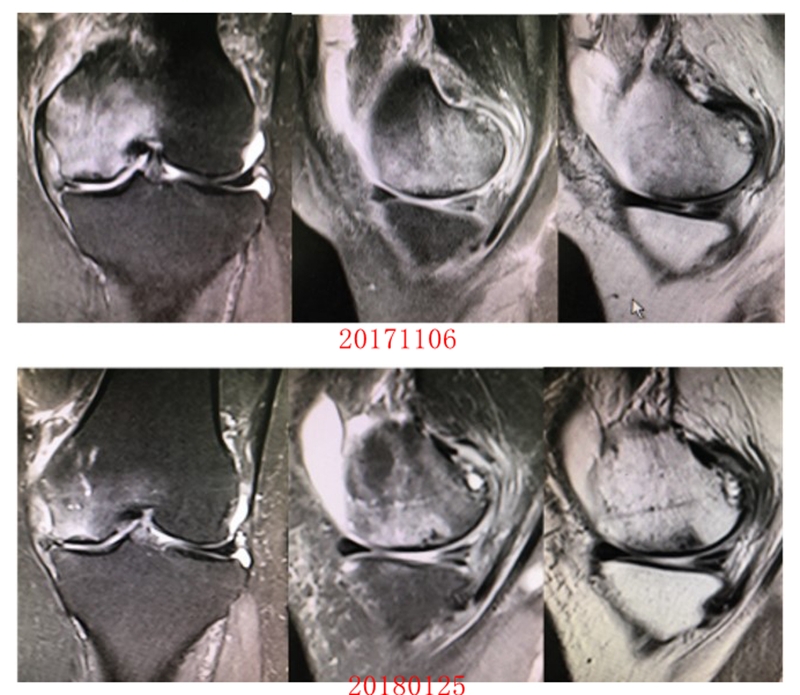

病例3:男,70岁,主诉右膝关节疼痛1年余。查体右膝无肿胀畸形,膝活动度0-120°,内侧间隙压痛。

已经累及44%的股骨内侧髁病变,半月板轻度突出,内侧后角水平撕裂

MRI上深度>20mm

治疗选择保守还是手术?

保守治疗4个月后复查

保守治疗后效果欠佳,坏死范围扩大、塌陷